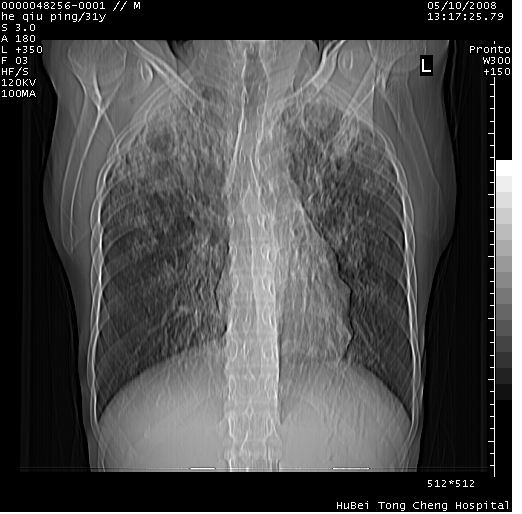

标题: CT13402:M,31Y。肺结核伴空洞形成? [打印本页]

标题: CT13402:M,31Y。肺结核伴空洞形成?

咳嗽半月余,消瘦体质,呼吸音弱。无其他病史。cr:肺转移瘤待。